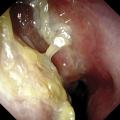

Polypose nasosinusienne

La polypose nasosinusienne est une rhinosinusite diffuse caractérisée par la présence de polypes bilatéraux dans les cavités nasales venant du massif ethmoïdal. Sa physiopathologie repose sur une inflammation chronique de la muqueuse des cavités nasales et sinusiennes marquée par une infiltration éosinophilique plus ou moins…